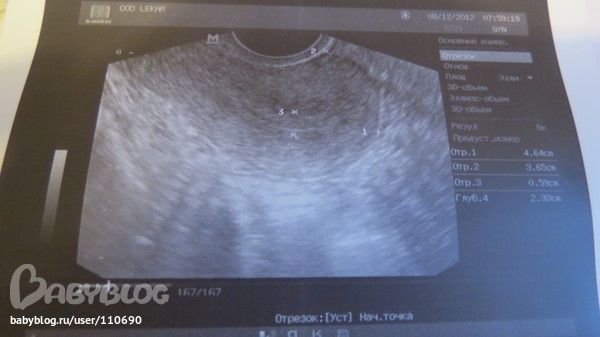

Ну вот и сходила на Фолликулометрию

Да видимо мне повезло, т.к она увидела фолликул и там жалостливо посмотрела, так сожалела,что наверно он не вылупится((( но я пойду на узи на 21 день,хочу посмотреть, что узи покажет. Теперь только узи, строго 3 раза в месяц.Тесты больше не покупаю.